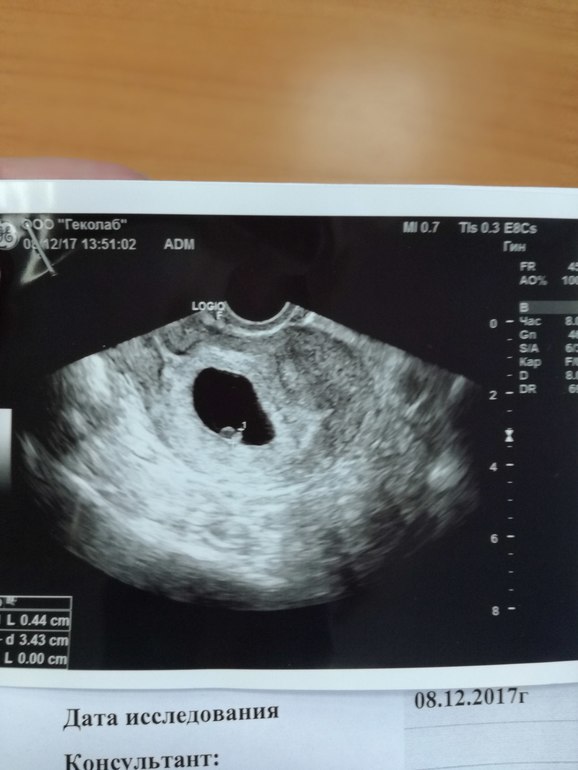

УЗИ, КТГ, доплерНе выдержала моя душа ждать до 8 недель. Сегодня 7 недель и 2 дня и я пошла платно на УЗИ, но не в МЕДОК, а в Инвитро на Сокольниках. Боялась, что будет мужик. Захожу - а там мужик. Думаю "Ну все, приплыли". Начал смотреть, минут 10 смотрел, с серьезным лицом и выдает "Ну тут срок примерно 5-6 недель". Я - "В смысле?!" Он - "Ну вот эмбриончик ваш, вот трубка у него пульсирует". И тут я выдаю "Вы меня прям спасли от нервного срыва, мне 3 узи показывали анэмбрионию". Он посмеялся и сказал "Просто молодые врачи невнимательные." И вправду, на прошлой фотке УЗИ я задавала вопрос врачу, а не это ли эмбрион, вот эта маленькая рисинка? Она мне сказала, что ничего подобного. И он сегодня там нашел нашего малыша. Долго смотрел на сердечко. Под одним углом аппарат узи выдает ритм 180, под другим - 104. Сказал, что он еще совсем крошечный, это не страшно, тут могут быть погрешности. Все рассказал, сказал что прикрепился немного низко, но это не страшно. Все в норме!!!! УРА!!!!!!!

Малышик прям позировал!